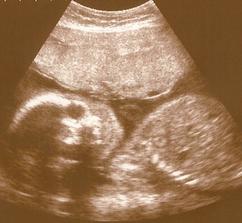

Naše milá rozrůstající se rodinka :o))

Začalo to v dubnu 1999 a zpečetili jsme to nejdříve narozením našeho syna Adámka a poté svatbou 1.10.2005, za chvíli budeme mít první výročí 🙂